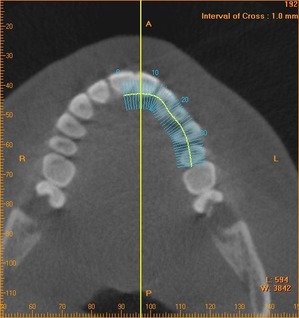

まずは通常のパノラマレントゲンでざっくりとチェックします

さらにCTを撮影して それぞれの根の状態をチェックします

ここでは省略しますが、顎の立体像を構築して 歯の関係と顎の関係もチェックしております